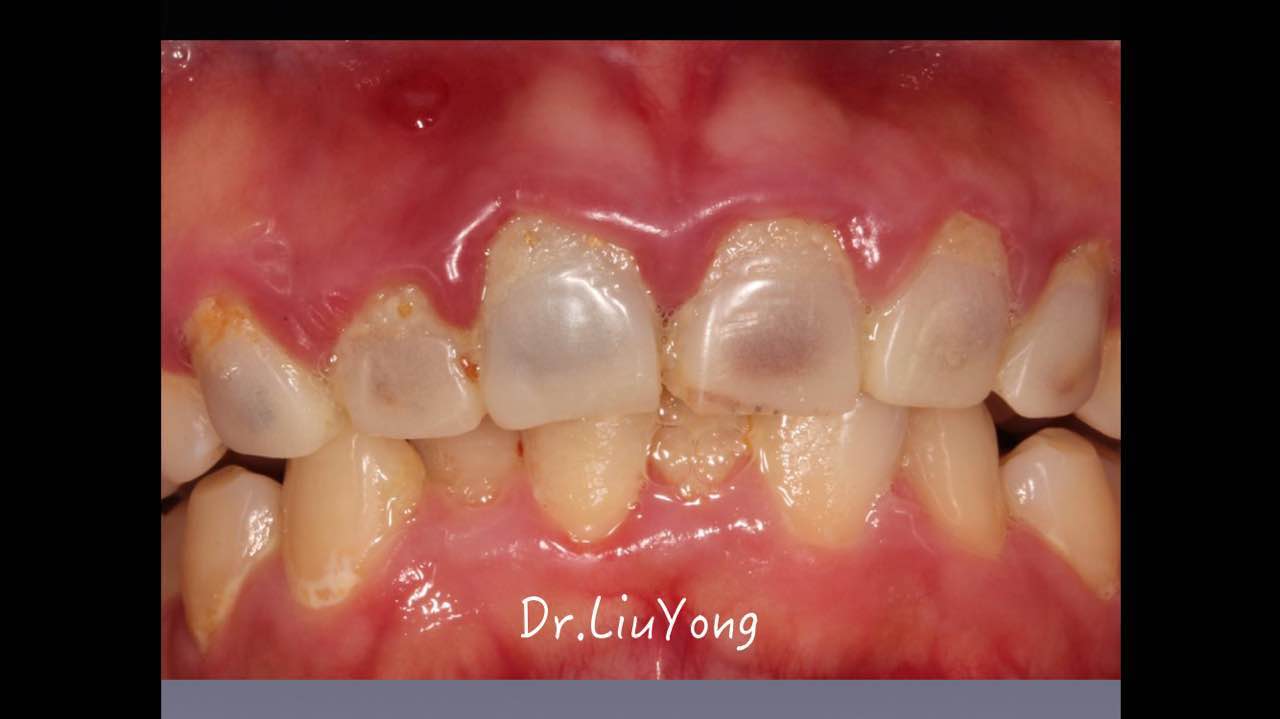

嚴重破壞生物學寬度,根尖瘺管,重行根管治療, 第一次冠延長建立唇腭側(cè)及鄰面BW,術后牙齦扇貝形差, 齦乳頭黑三角,再次行美學冠延長,建立牙齦扇貝形,手術免費, 患者因經(jīng)濟原因只能選擇鑄樁及鈷鉻合金烤瓷冠。終于完工